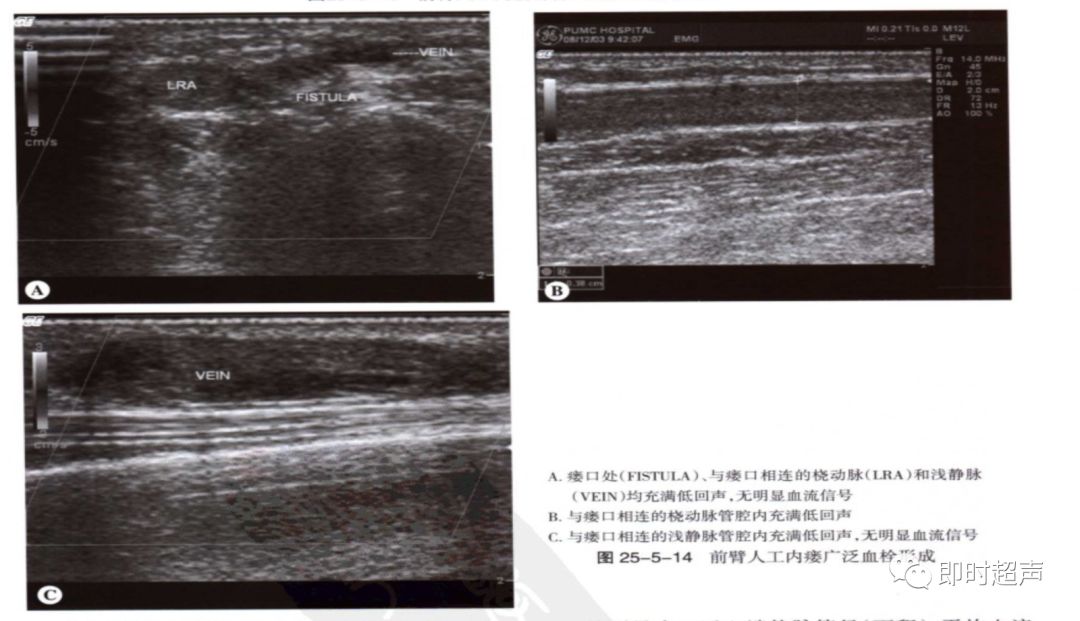

血栓:血栓与狭窄密切相关,常发于静脉侧,静脉管腔压瘪可除外血栓形成。闭塞处可见彩色多普勒血流中断,频谱多普勒信号消失。流入道动脉呈高阻频谱改变。

常见并发症-3